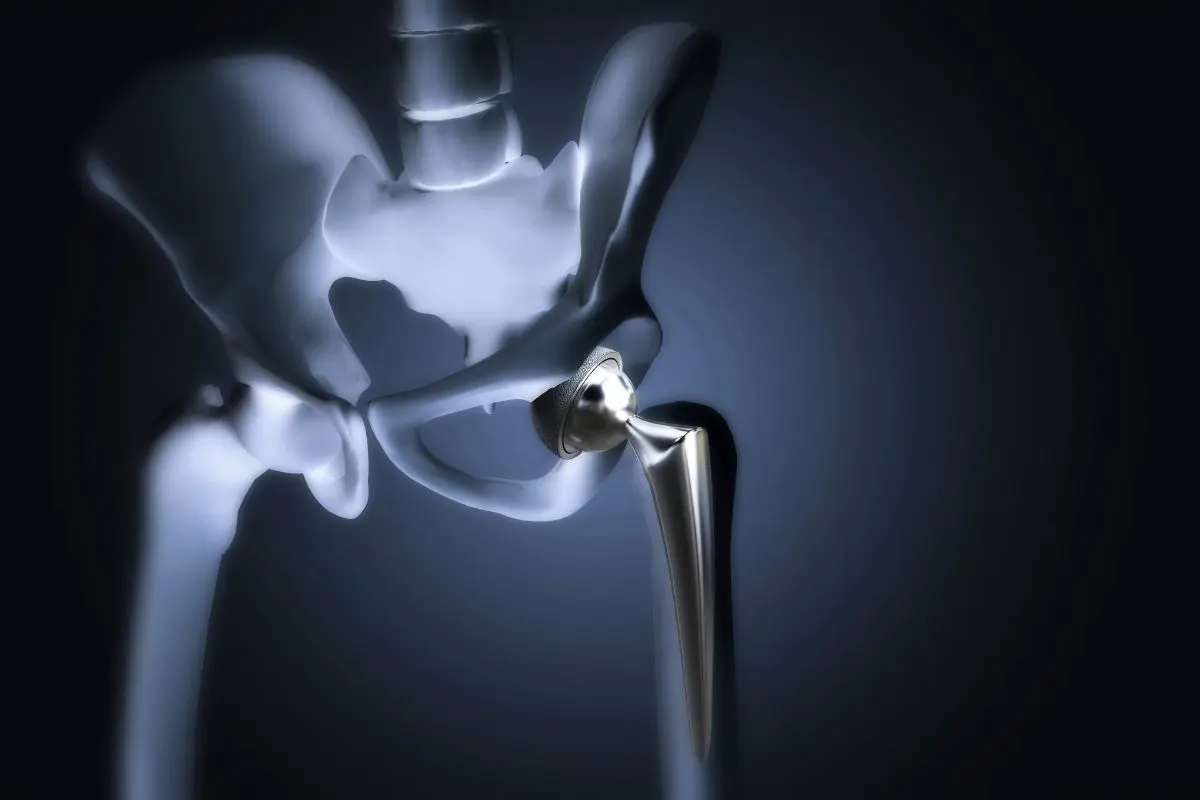

During the surgery, the orthopedic surgeon removes the damaged parts of the hip joint and replaces them with a hip prosthesis made of durable materials such as titanium, ceramic, or medical-grade plastic. These artificial components are designed to replicate the natural movement of the hip, helping patients move more comfortably and with less pain.

The prosthetic hip usually consists of three main components:

- A metal stem placed inside the thigh bone (femur)

- A ball component that replaces the damaged femoral head

- A socket component that replaces the damaged hip socket

These components are made from durable materials such as titanium, ceramic, or medical-grade plastic, allowing the artificial joint to move smoothly and withstand years of use.